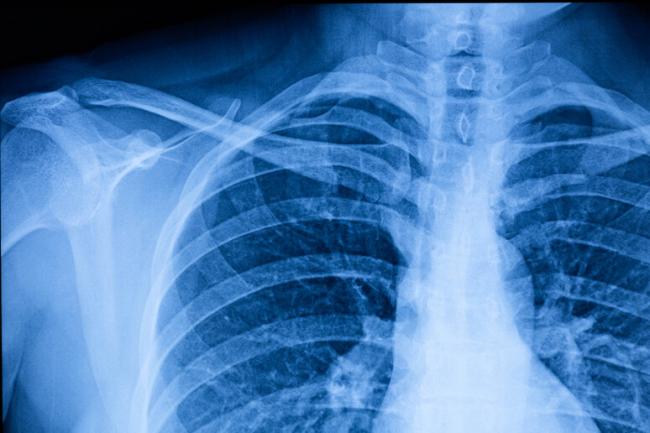

L’intelligenza artificiale (IA) sembra riuscire a stimare l’età anche dal torace. Lo dimostra l'algoritmo sviluppato presso l'Università Metropolitana di Osaka, in Giappone, che in un articolo pubblicato sulla rivista The Lancet Healthy Longevity dimostra che le radiografie del torace possono essere utilizzate per stimare con precisione l'età cronologica, cioè il tempo trascorso dalla nascita in poi. il tutto per individuare i primi segnali di malattie croniche come l'ipertensione.

Una delle applicazioni più potenti degli algoritmi di intelligenza artificiale è la capacità di analizzare milioni e milioni di dati, cercando di identificare schemi che l’occhio umano non è in grado di rilevare, come la correlazione di impercettibili cambiamenti nel suono con possibili patologie della gola. Questi sono modelli che possono essere trovati in molti test medici, come le radiografie, e sta analizzando fino a 67.099 radiografie del torace di 36.051 individui sani sottoposti a controlli sanitari presso tre strutture mediche.

Il sistema di intelligenza artificiale sviluppato dai ricercatori giapponesi è riuscito a stimare l'età cronologica dei pazienti, cioè il tempo effettivamente trascorso dalla nascita, con un coefficiente di correlazione pari a 0,95, praticamente con un livello di precisione molto elevato.

Dati dai quali l’IA ha dimostrato anche un’altissima capacità nella diagnosi precoce dello sviluppo di malattie croniche che colpiscono il torace in modi diversi, come l’ipertensione, l’iperuricemia e le malattie polmonari croniche ostruttive.